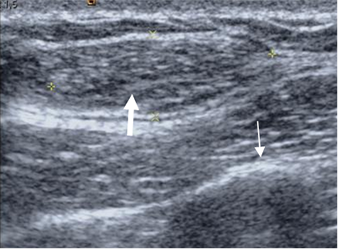

Fig 41. Lipoma.

Ecografía. Lesión sólida, superficial y de bordes definidos en la pared costal , compatible con lipoma (Flecha gruesa) y en relación con la costilla (Flecha delgada).